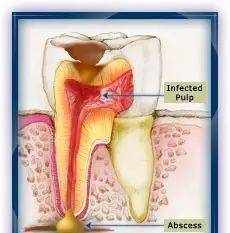

牙神经或牙髓组织所在空间密闭,通过狭窄的根尖孔与外界血运交通,遇到感染后自我愈合的能力非常有限。来自牙冠方的细菌一旦侵袭到牙髓腔,很容易大量繁殖,随后感染向深部扩散,穿出根尖孔后形成牙根根尖脓肿。

牙髓感染可造成的后果:

"感染向根方扩散导致牙槽骨的吸收;

"形成从根尖病变区通向牙龈甚至面部的窦道或瘘管(脓液引流);

"感染可扩散至头、颈和面部;

因此牙髓一旦感染或经医生判断将会感染的情况下,需要对患牙做根管治疗以防发生严重后果。

牙神经或牙髓组织所在空间密闭,通过狭窄的根尖孔与外界血运交通,遇到感染后自我愈合的能力非常有限。来自牙冠方的细菌一旦侵袭到牙髓腔,很容易大量繁殖,随后感染向深部扩散,穿出根尖孔后形成牙根根尖脓肿。

牙髓感染可造成的后果:

"感染向根方扩散导致牙槽骨的吸收;

"形成从根尖病变区通向牙龈甚至面部的窦道或瘘管(脓液引流);

"感染可扩散至头、颈和面部;

因此牙髓一旦感染或经医生判断将会感染的情况下,需要对患牙做根管治疗以防发生严重后果。